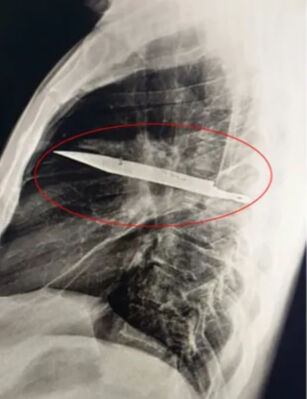

Röntgende adamın göğsünde saplı duran bir bıçak olduğu görüldü. Bunun üzerine açıklamalarda bulunan hasta, yaklaşık 8 yıl önce karıştığı bir kavga sırasında yüzünden, sırtından, göğsünden ve karnından yaralandığını, o zaman tedavi gördüğünü, ancak bıçağın saplandığını fark etmediklerini söyledi. O günden bu yana ciddi bir sağlık sorunu yaşamadığını söyleyen adam, gördükleri karşısında şaşkına döndü.

The Sun’ın haberine göre, sağ kürek kemiğinden girip hayati organlara zarar vermeden göğüste saplı kalan bıçak, acil ameliyatla alındı.